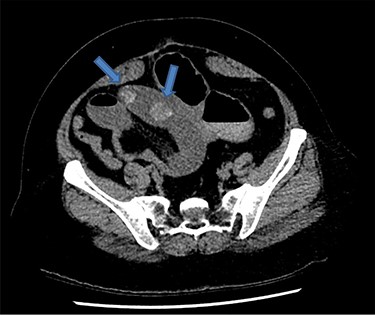

There were associated vomiting and abdominal distension. Her last bowel movement was 12 hours prior to the presentation, and she passed minimal flatus since. She has a background of chronic kidney disease. She was slightly tachycardic in ED. Abdominal examination demonstrated a mildly distended and soft abdomen with left lower quadrant tenderness without peritonism. Blood work showed an acute on chronic renal failure (creatinine 198 μmol/l and estimated glomerular filtration rate 24 ml/min/1.73 m2). Liver function tests were mildly deranged (bilirubin 27 μmol/l, alkaline phosphatase 105 U/l, GGT 85 U/l, alanine aminotransferase 38 U/l, aspartate aminotransferase 37 U/l) and white cell count was slightly elevated (10.7 × 109/l; reference range 3.7–9.5 × 109/l). Computed tomography (CT) scan (Figs 1 and 2) demonstrated multiple loops of moderated dilated small bowel. There were two 25-mm gallstones in a loop of small bowel in the right lower quadrant. The gallbladder is collapsed with intraluminal gas. There was pneumobilia in the biliary tree. The features on CT are in keeping with a gallstone ileus. Initial management included fluid resuscitation, insertion of a nasogastric tube, analgesia and nil by mouth. A Foley catheter was inserted to monitor urine output. A laparotomy proceeded within 24 hours. Two palpable gallstones were found within the distal ileum. A longitudinal enterotomy was made immediately proximal to the point of calculus impaction and two calculi were delivered from the bowel lumen (Fig. 3). There was a suspected calculus contained within the gallbladder. However, the decision was made not to proceed for further reduction via the fistula due to significant risk of duodenal injury. Her recovery was uneventful, and renal function returned to baseline. She was discharged home 7 days after her operation. During the outpatient clinic follow-up, an interval cholecystectomy and cholecystoduodenal fistula closure had been arranged in 4–6 months after her initial operation.

Coronal CT image demonstrates gallstones (blue arrow) (only one gallstone shown on this image) in a loop of small bowel in the right lower quadrant.